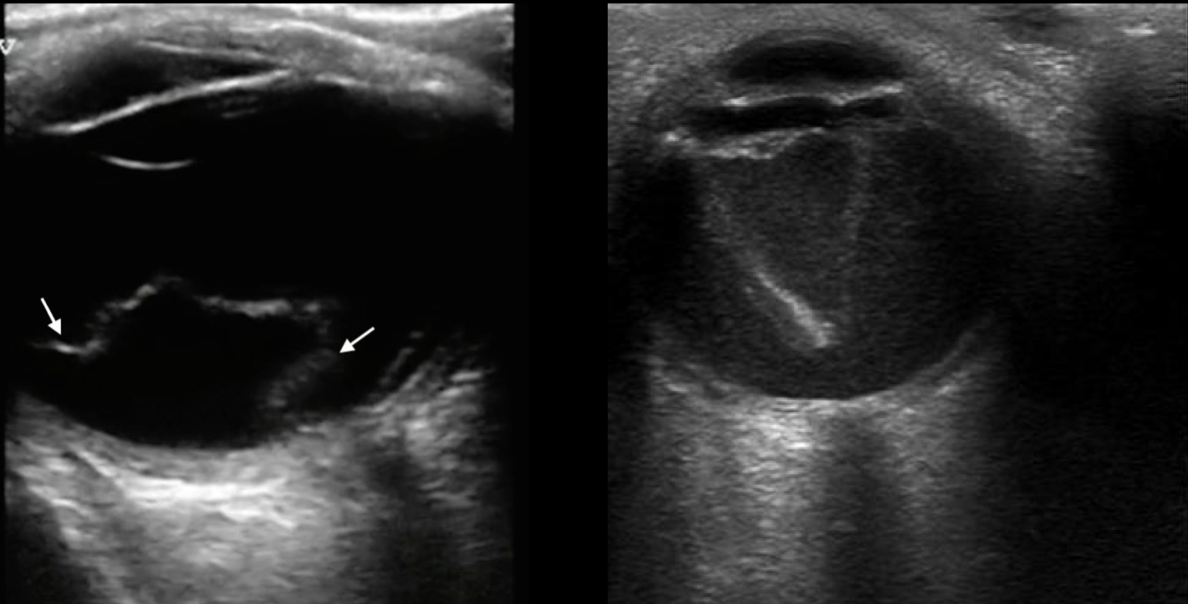

Retina doblada y brillante

Movimientos disminuyen

A

US en desprendimiento de retina